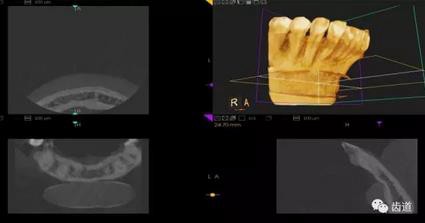

CBCT在牙種植修復(fù)中的應(yīng)用。種植前利用CBCT對(duì)患者的牙床進(jìn)行檢查,可精準(zhǔn)判斷牙槽骨的寬度、厚度及高度、骨的密度、重要的顏面神經(jīng)、血管和鼻竇位置等。臨床醫(yī)生不僅可以在計(jì)算機(jī)直觀的看到牙槽骨的立體影像,還可以切換不同的視角來(lái)觀察硬組織之間的位置關(guān)系,在手術(shù)方案中避開(kāi)危險(xiǎn)區(qū)域,保證手術(shù)的安全性。臨床醫(yī)生還可以利用CT數(shù)據(jù)進(jìn)行數(shù)字模型重建,配合軟件預(yù)先做好手術(shù)模板,使種植手術(shù)更安全快捷,避免在種植手術(shù)過(guò)程中不慎破壞神經(jīng)、鼻竇等解剖結(jié)構(gòu),導(dǎo)致顏面神經(jīng)麻痹、鼻竇炎等并發(fā)癥的發(fā)生。

1、下頜骨種植牙前測(cè)量準(zhǔn)備影像

2、上頜骨種植牙前準(zhǔn)備影像